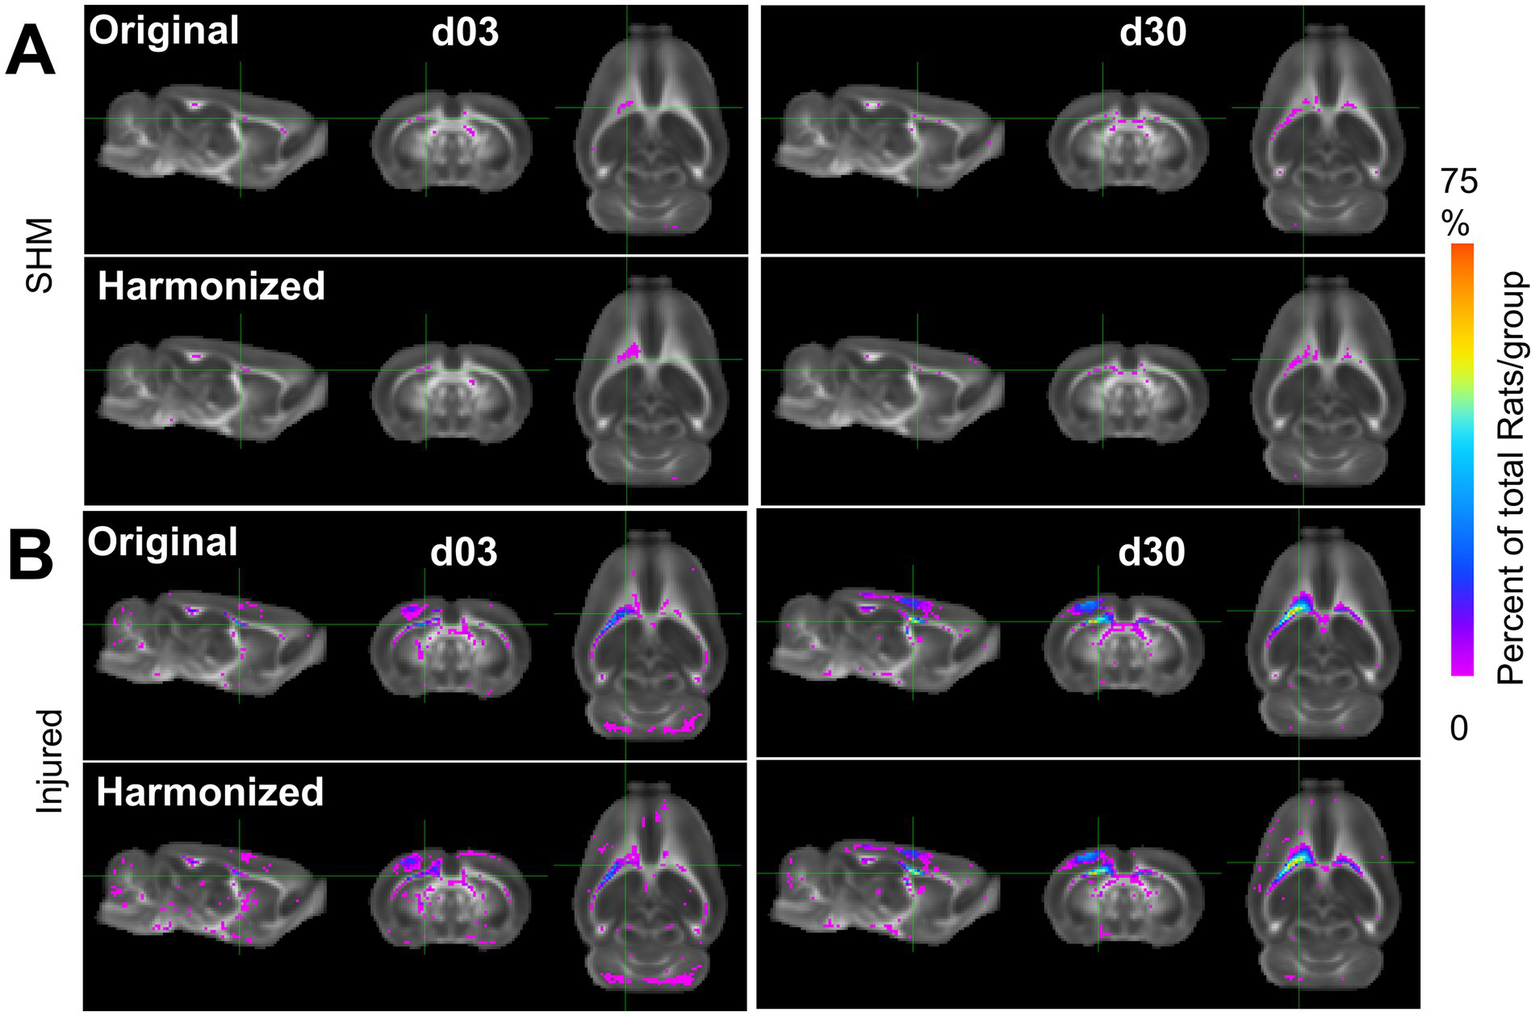

Figure 9

Multi-Site Voxel overlap maps delineating larger regions of common pathology due to data harmonization. (A) Sham and (B) Injured voxel overlap maps derived from whole-brain data with all three sites showing the incidence of the number of rats at each voxel location where FA values differ significantly from pooled sham data before (label-Original) and after harmonization (label-Harmonized). Images show voxels where there was a lower (Pink) and higher (Blue/Red) proportion of CCI rats in which the FA value was significantly different from pooled shams due to data harmonization (p < 0.01, FDR corrected).

We sought to determine whether the improved power and effect size was underpinned by the detection of pathologically low or high FA when compared to the sham group. FA voxel overlap maps showing the proportion of rats with FA values significantly different from sham after harmonization versus before, revealed an increased number, and overlap of rats after harmonization when compared to the original data (Figure 9). These increases were especially prevalent within, and adjacent to, the primary, ipsilateral injury area. All differences detected were related to decreases in FA; no data was underpinned by increased areas of FAHigh when compared to shams. These results indicate that cross-site data harmonization can improve the reliability of group differences in the areas surrounding the primary injury area at the cost of lower power in regions more remote from the primary injury site. For other scalar measures, results were markedly different. Generally, the proportion of rats significantly different from mean sham was lower. In the AD dataset, most areas of difference were found in the ipsilateral cortex, frontal pole and cerebellum. The only location to produce an increase in the number of rats was a small portion of the corpus callosum. In other areas, harmonization decreased the number of voxels with significant differences, suggesting an initially weak effect at both day 3 and 30 (Supplementary Figure S5). Similarly, the MD data at day 3 showed large portions of the cortex with a small number of rats being significantly different from sham, but this area decreased after harmonization. At day 30, the number of voxels increased around pre-existing areas of difference in the cerebellum and parts of the ipsilateral cortex (Supplementary Figure S10). In the RD dataset, areas of pre-existing cortical differences decreased after harmonization at day 3 and day 30, except for minor increases in coverage in the contralateral cerebellum (Supplementary Figure S15).